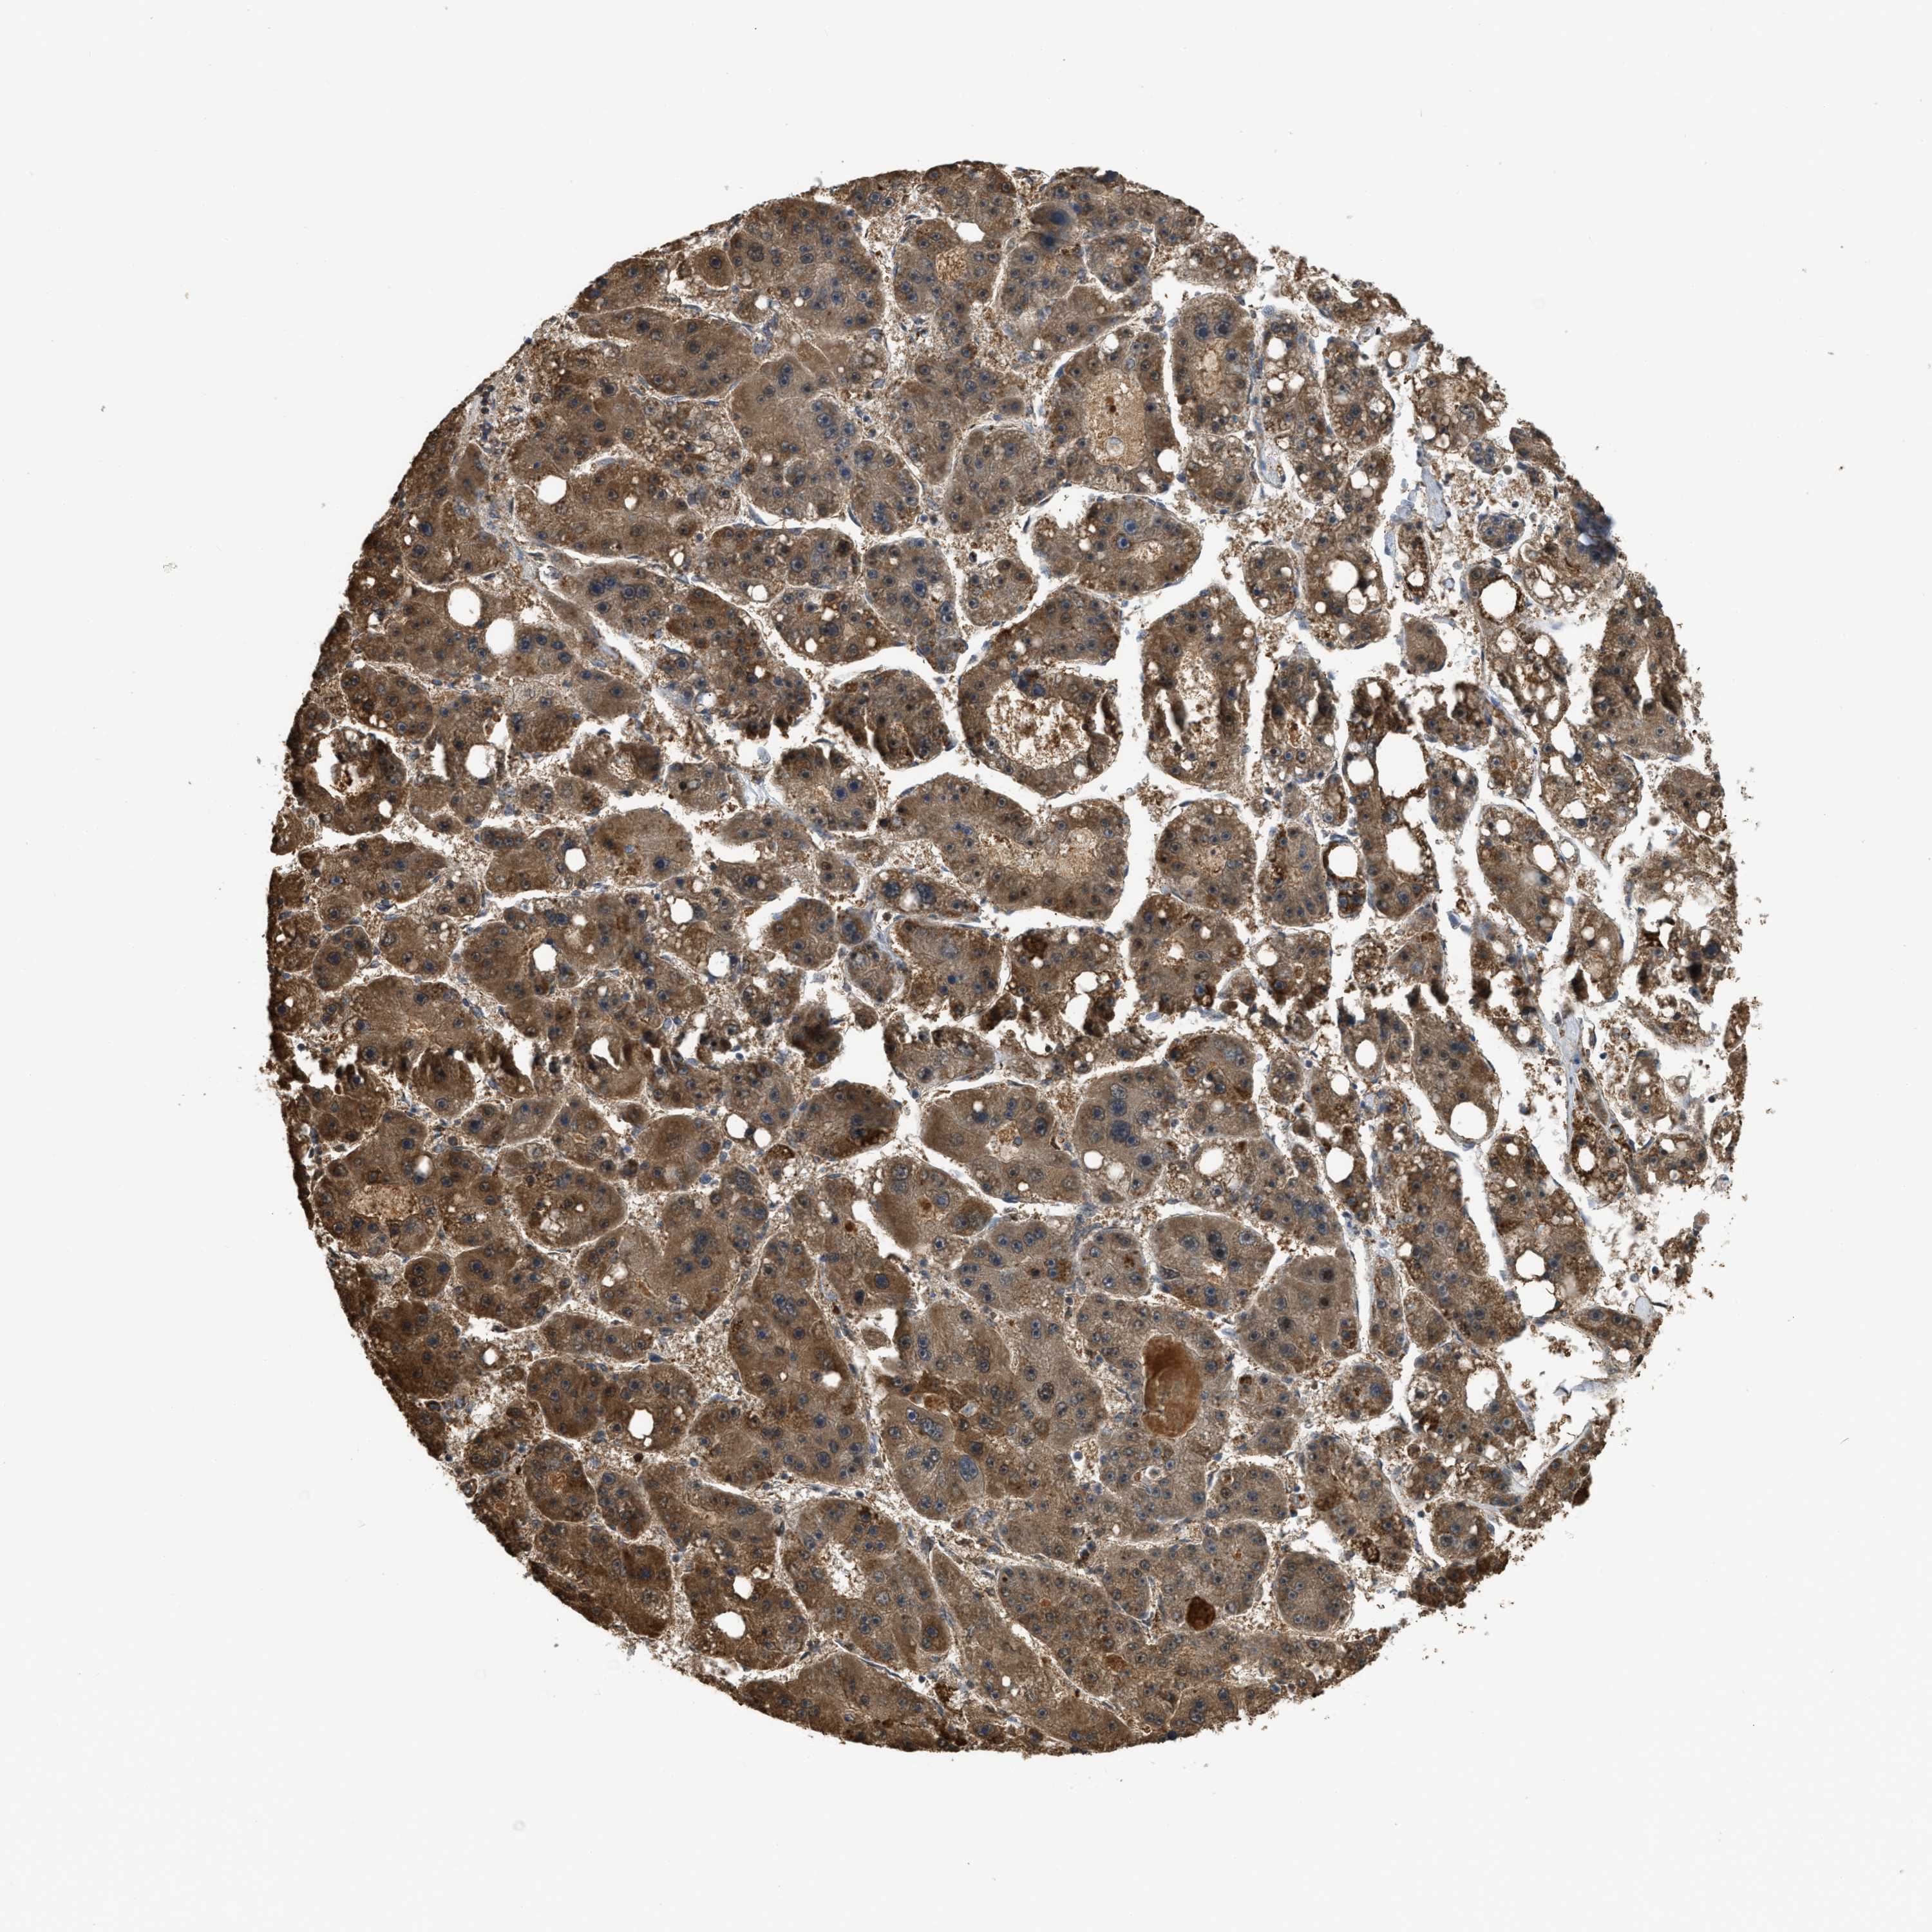

LIVER CANCER - Protein expressioni

A mouse-over function shows sample information and annotation data. Click on an image to view it in a full screen mode. Samples can be filtered based on level of antibody staining by selecting one or several of the following categories: high, medium, low and not detected. The assay and annotation is described here.

Note that samples used for immunohistochemistry by the Human Protein Atlas do not correspond to samples in the TCGA dataset.

Antibody stainingi

Antibody staining in the annotated cell types in the current human tissue is reported as not detected, low, medium, or high, based on conventional immunohistochemistry profiling in selected tissues. This score is based on the combination of the staining intensity and fraction of stained cells.

Each image is clickable and will lead to virtual microscopy that enables deeper exploration of all samples and also displays staining intensity scores, fraction scores and subcellular localization as well as patient and tissue information for each sample.

Antibody HPA018910

Antibody HPA018921

Antibody HPA018923

Staining

High

Medium

Low

Not detected

Intensity

Strong

Moderate

Weak

Negative

Quantity

>75%

75%-25%

<25%

None

Location

Nuclear

Cytoplasmic/membranous

Cytoplasmic/membranous,nuclear

Cholangiocarcinoma

Carcinoma, Hepatocellular, NOS